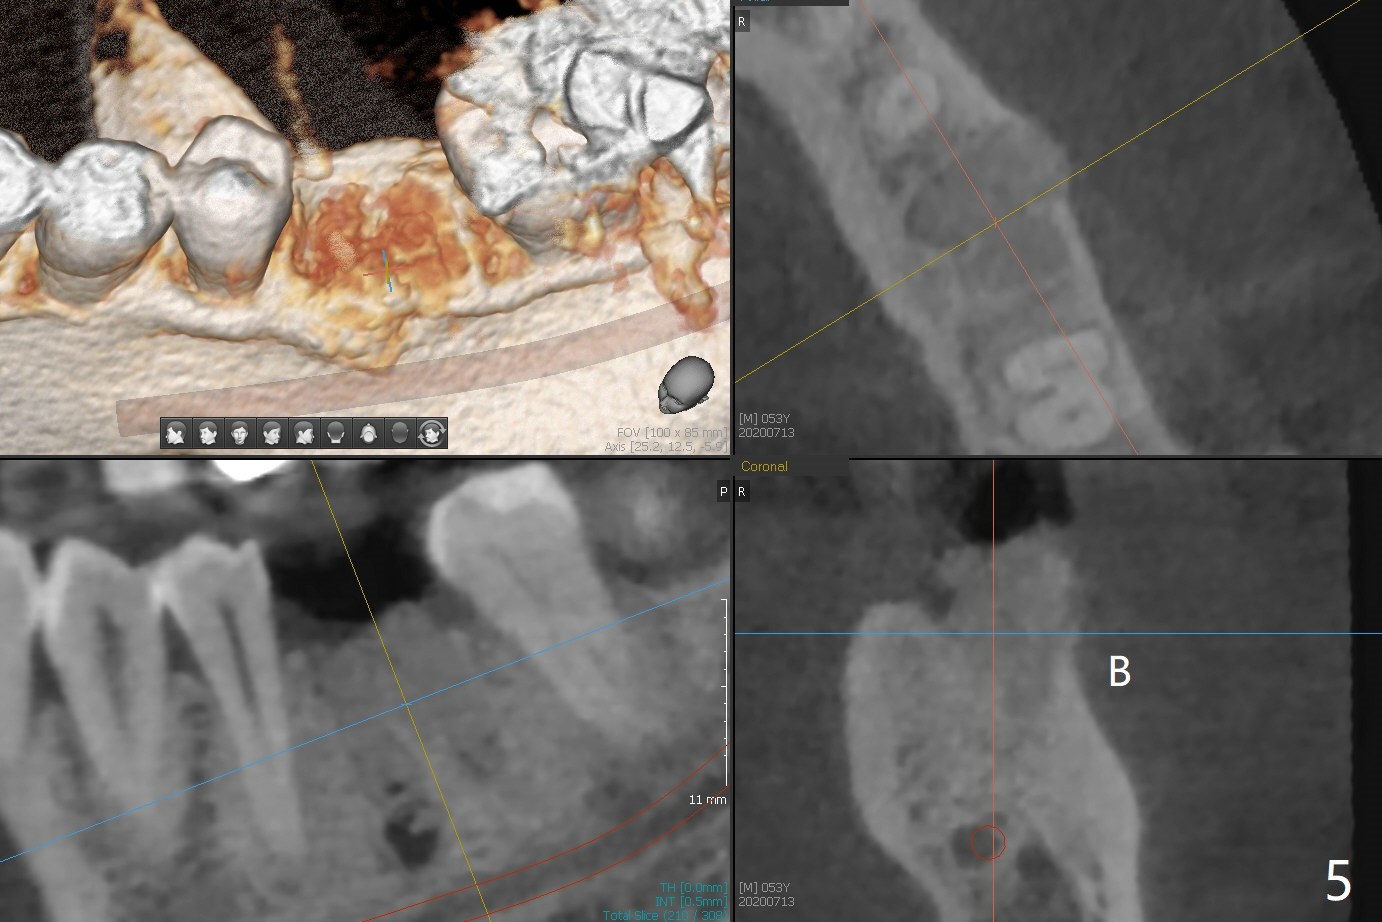

When the patient returns for #15 comp, the bone resorption and swelling at #19 are worse than those 3 years ago (Fig.1,2). After debridement, the mesial socket is large, while the septum is thin, irregular and with undercut (Fig.3). It seems difficult to obtain primary stability for an immediate implant. Vanilla bone and cortical bone hydrated with GEM21 S are placed for socket preservation (Fig.4,5), followed by 12x12 mm BioXclude and 4/0 PGA. In fact the bone height is limited for an immediate implant (Fig.6 (5x10 mm)). There is not enough bone in the septum for primary stability (Fig.7 (cross section of 3D image; L: lingual)). The socket heals 16 days postop (Fig.8). It appears that the granulation tissue is covered by a thin layer of granulation tissue (Fig.9 *), while the membrane remains in place (M). In fact the bone graft remains in the soft tissue zone as well as the hard tissue one (Fig.10). In spite of no apparent loss of bone graft (Fig.4,10), the graft seems to shrink in height 3.5 months postop (Fig.11), while the crest decreases (compare Fig.1 and 11). The keratinized gingiva is wide, but the alveolus reduces in width (Fig.12). The buccal crestal bone is lost 3.5 months postop (Fig.13).